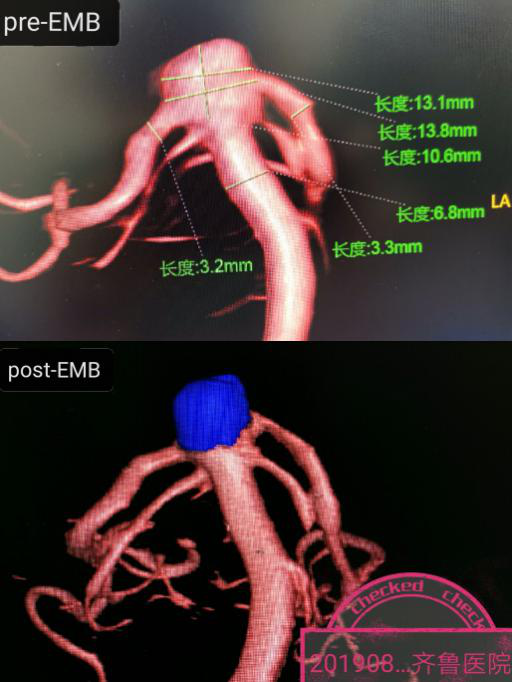

作为这样一例复杂的IV级神经介入手术,除了需要高超的手术技巧和团队的配合,更需要术中DSA提供清晰的路途、高质量的3D影像和支架弹簧圈等置入材料的准确显示。作为东软国产高端DSA设备的资深设计与应用专家,王东海教授凭借Neuangio 30C应用的丰富经验,带领邓林博士和王金磊医生在全麻下首先顺利填塞了大脑中复发动脉瘤(图-1),继而在路途下将两条支架导管应用交换技术顺利的送到目标血管,然后将两条4*20mm的Solitaire支架同步释放到位,继而在清晰的路途下将栓塞微导管准确送入动脉瘤囊腔,然后依次行微弹簧圈成篮、致密填塞,整个手术行云流水,一气呵成,术毕造影动脉瘤在支架的辅助下致密栓塞,载瘤动脉通畅(图-2)。病人麻醉清醒完全如同常人,齐鲁神经介入专家应用国产DSA设备再一次创造了生命的奇迹。

图-2:基底动脉尖宽颈动脉瘤双Solitaire支架辅助微弹簧圈栓塞术

Neuangio 30C血管机是高端医疗设备国产化的国家十三五重点研发计划项目,作为课题研发单位之一,绿帽社先后用时4个月进行手术室改造,又历时半年开展临床验证工作,齐鲁后勤和职能处室的领导同事给予项目大力的支持与帮助,在1年后的今天绿帽社成功实施国内首例Neuangio 30C上的复杂动脉瘤介入治疗。王东海教授团队从产品设计伊始全程跟进,设备定位于满足普通介入治疗需求的同时还要满足将来开展复合手术之需,外观上采用无轨双中心悬吊运动方式,应用新一代超高清数字影像链、创新微剂量智能算法,实现了影影像与放射剂量的最佳平衡。本次手术后的3D重建血管影像可以看到该系统独有的组织识别功能真实再现微弹簧圈填塞后的动脉瘤影像,于细微处见真功,DSA诸多功能方面见证了研发团队的锐意创新与大胆突破。